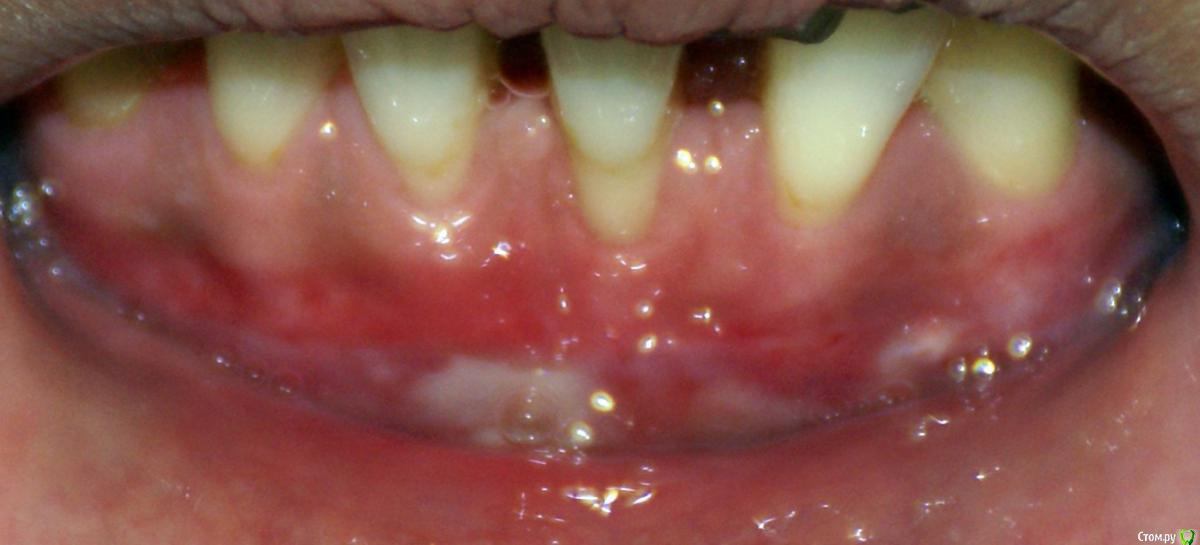

Irina_S Опубликовано 15 июня, 2017 Поделиться Опубликовано 15 июня, 2017 Здравствуйте, уважаемые специалисты! Заранее прошу прощения за не слишком качественные фото! Почти восемь месяцев назад мне была сделана вестибулопластика на нижней челюсти.За пять дней до операции ситуация во рту выглядела так: Для проведения операции были такие показания: Вот ещё описание самой операции, которая была 24 октября 2016 г.: Через шесть дней после операции: Ещё через шесть дней, 5 ноября: Прошла ещё неделя, 12 ноября: Следующий раз фото, к сожалению делалось через три с лишним недели, 4 декабря, в разных ракурсах: После этого визуальные изменения касались только уменьшения белёсых мест от разреза.Вот состояние на 10 июня этого года с разными вариантами оттягивания губы: По результатам заживления я не вижу разницы в глубине преддверия, ради чего и проводилась операция.К тому же всё время с момента операции присутствуют стягивающие ощущения и ощущение инородного тела в подбородке. Ответьте, пожалуйста, правильно ли была сделана операция вестибулопластики?Спасибо за внимание! Ссылка на комментарий

dok1 Опубликовано 15 июня, 2017 Поделиться Опубликовано 15 июня, 2017 (изменено) Пусть глубокого преддверия и не достигли, но тяж центальный убрали. Но и преддверие стало глубже немного. Результат, на мой взгляд, удовлетворительный вплне. Тоже без претендования на абсолютную истину. Изменено 15 июня, 2017 пользователем dok1 Ссылка на комментарий

колесников Опубликовано 15 июня, 2017 Поделиться Опубликовано 15 июня, 2017 По уровню прикреплённой десны ситуация выглядит лучше,стабильнее чем до вмешательства. После вмешательств такого рода часто случаются рецидивы и неудачи,у Вас их нет. Но случаются и побочные "осложнения",в частности у Вас образовались тяжи в области клыков,которых раньше не было. Запргнозировать их оборазование зачастую невозможно. Это мягкие ткани,их можно попробовать "растянуть" или размягчить,делая миогимнастику,(надувая пузырь под губой),если это не поможет,дополнительная пластика по устранению этих тяжей. Ссылка на комментарий